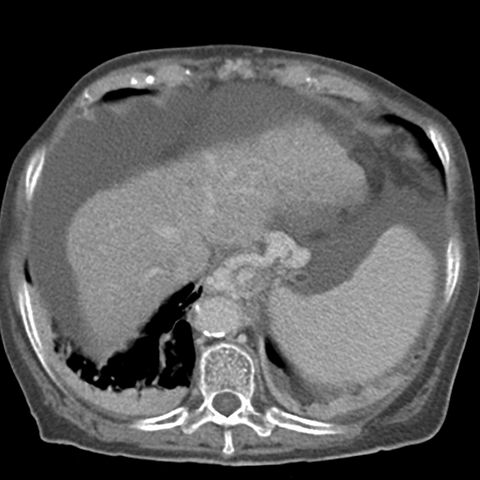

Cirrhosis and Portal Hypertension, CT ( axial ) [2 of 3]